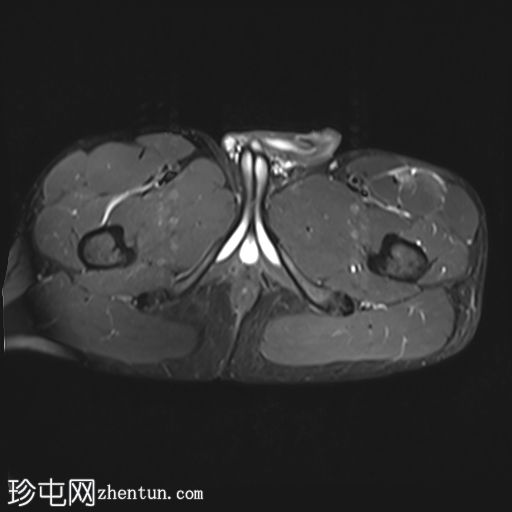

轴位

T1加权像

T2加权像

股直肌近端和中段前外侧可见一水肿性高信号影,长约15厘米,宽约3厘米。肌纤维轻度分离,但未见撕裂。肌内未见积液;在相邻肌间隙可见一条细小的液线环绕肌肉,延伸至近端肌腱交界处。

股直肌中段的间接肌腱轻度增厚,伴有肌腱周围水肿,提示2B级拉伤。但肌腱保持连续性,骨性附着良好,未见撕裂。